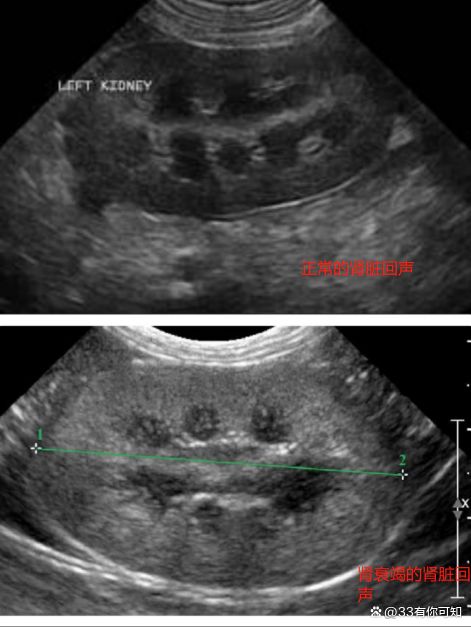

Answer6:早期多饮多尿、嗜睡、食欲变差、躯干肌肉减少、被毛杂乱掉毛、消瘦、呕吐、口臭、粘膜苍白贫血。严重时会出现严重脱水眼球凹陷、走路摇摆、失禁、呕吐、精神呆滞、反应迟钝、因为长期高血压导致失明、抽搐、多藏、少年或者无尿。但这些都是肾衰比较明显的时候出现的,但肾脏损伤超过40%左右的时候,其实临床症状并不明显,猫咪能吃能喝,体重短时间内变化也并不大,所以,早期要想排查猫咪有无肾功能不良,主要是检查SDMA和超声检查肾实质有没有纤维化病变回声增高。

Answer7:抽血测量肌酐、尿素、SDMA、超声检查肾脏有无纤维化病变回声增高、尿液检查尿蛋白肌酐比、尿比重。读过我之前文章的朋友应该都知道。肌酐上升提示肾损伤超过75%会出现、SDMA升高提示肾损伤超过40%、无机磷、肌酐都升高提示肾损伤超过了85%。